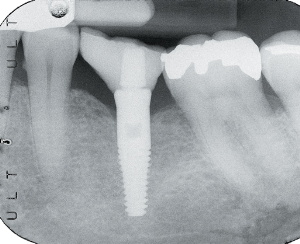

At 2 months the patient returned for a quick, 5-minute examination. A periapical radiograph was obtained to verify an intimate bone-to-implant surface contact. The implant was also examined physically and visually for mobility, pain, and signs of infection. If the examination demonstrates a lack of mobility, pain, and/or infection, and demonstrates intimate bone-to-implant contact, progressive osseointegration; is established, paving the way for prosthetic delivery (Figure 6).

The patient was now scheduled for a 30-minute prosthetic seating appointment. It was not necessary to anesthetize the patient for this phase of the treatment. The healing cover was removed, and the hex hole recess in the implant was gently dried. A small amount of resin cement was dispensed, mixed, and applied to the hex hole recess in the implant with a slender, pointed resin application brush and wiped onto the inner walls of the hex hole in a circular motion. The resin crown post;core assembly was then seated into the implant and allowed to set. Cement flash was removed, and if required, the occlusion was adjusted at this time. For this case, Rely-X resin cement (3M ESPE) was chosen for cementation because of its ease of use and excellent performance (Figures 16 and 17).